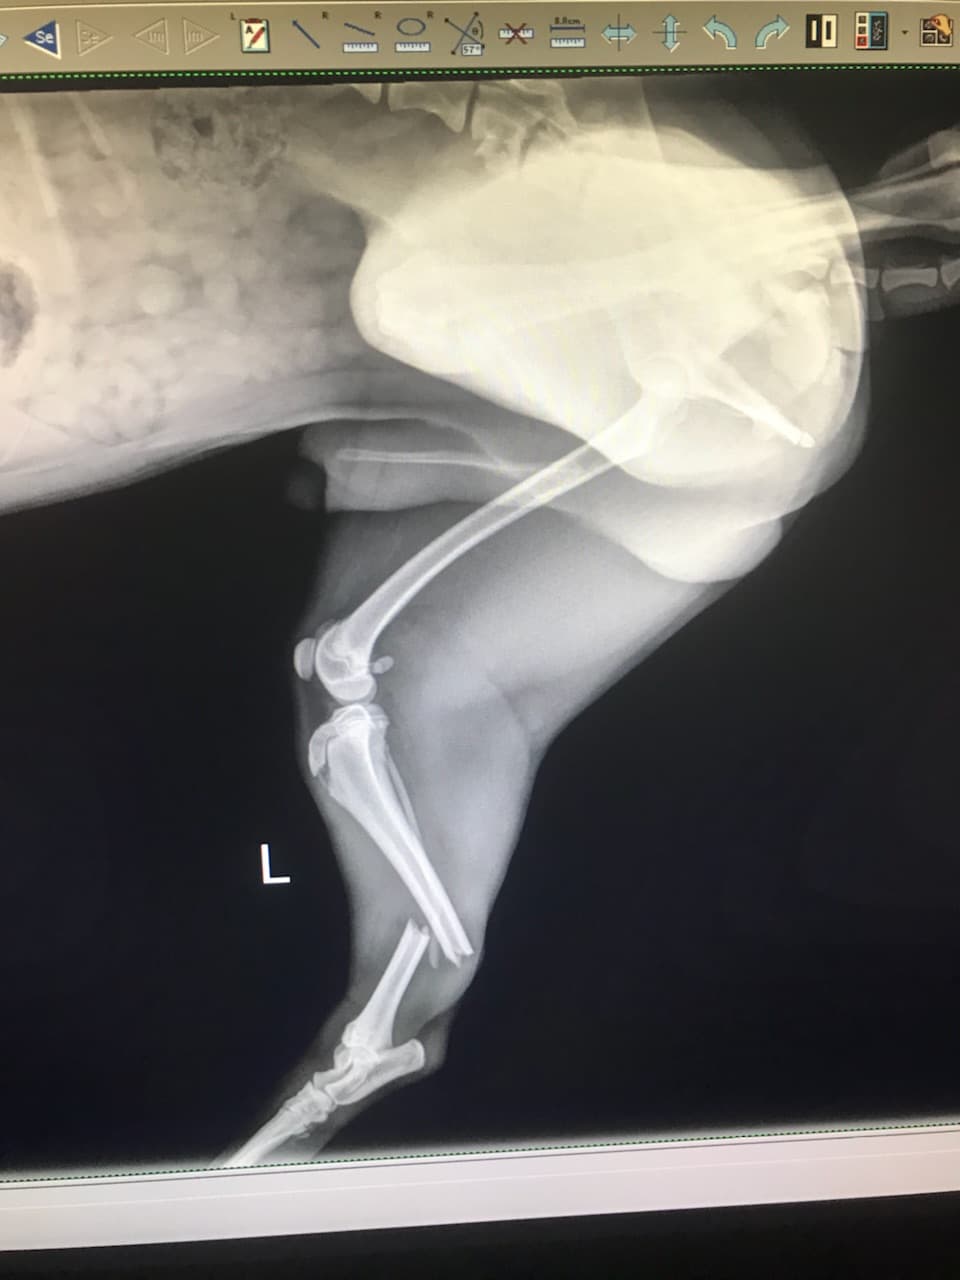

05/03/18- When I was at work, Maple got out of the house and ran out into the street (Bolsa and Bushard) and was hit by an oncoming vehicle. Fortunately Maple survived but was left with a broken leg and damaged spine. The vet said that it would cost 3k for the leg surgery and 7k for the spine surgery and I don't have the money to pay for his medical expenses. I know that people are always fundraising for other causes but if you can even spare a dollar, I would really appreciate it. He's the reason I wake up everyday with a smile. He's the happiest dog in the world and seeing him so sad breaks my heart =((